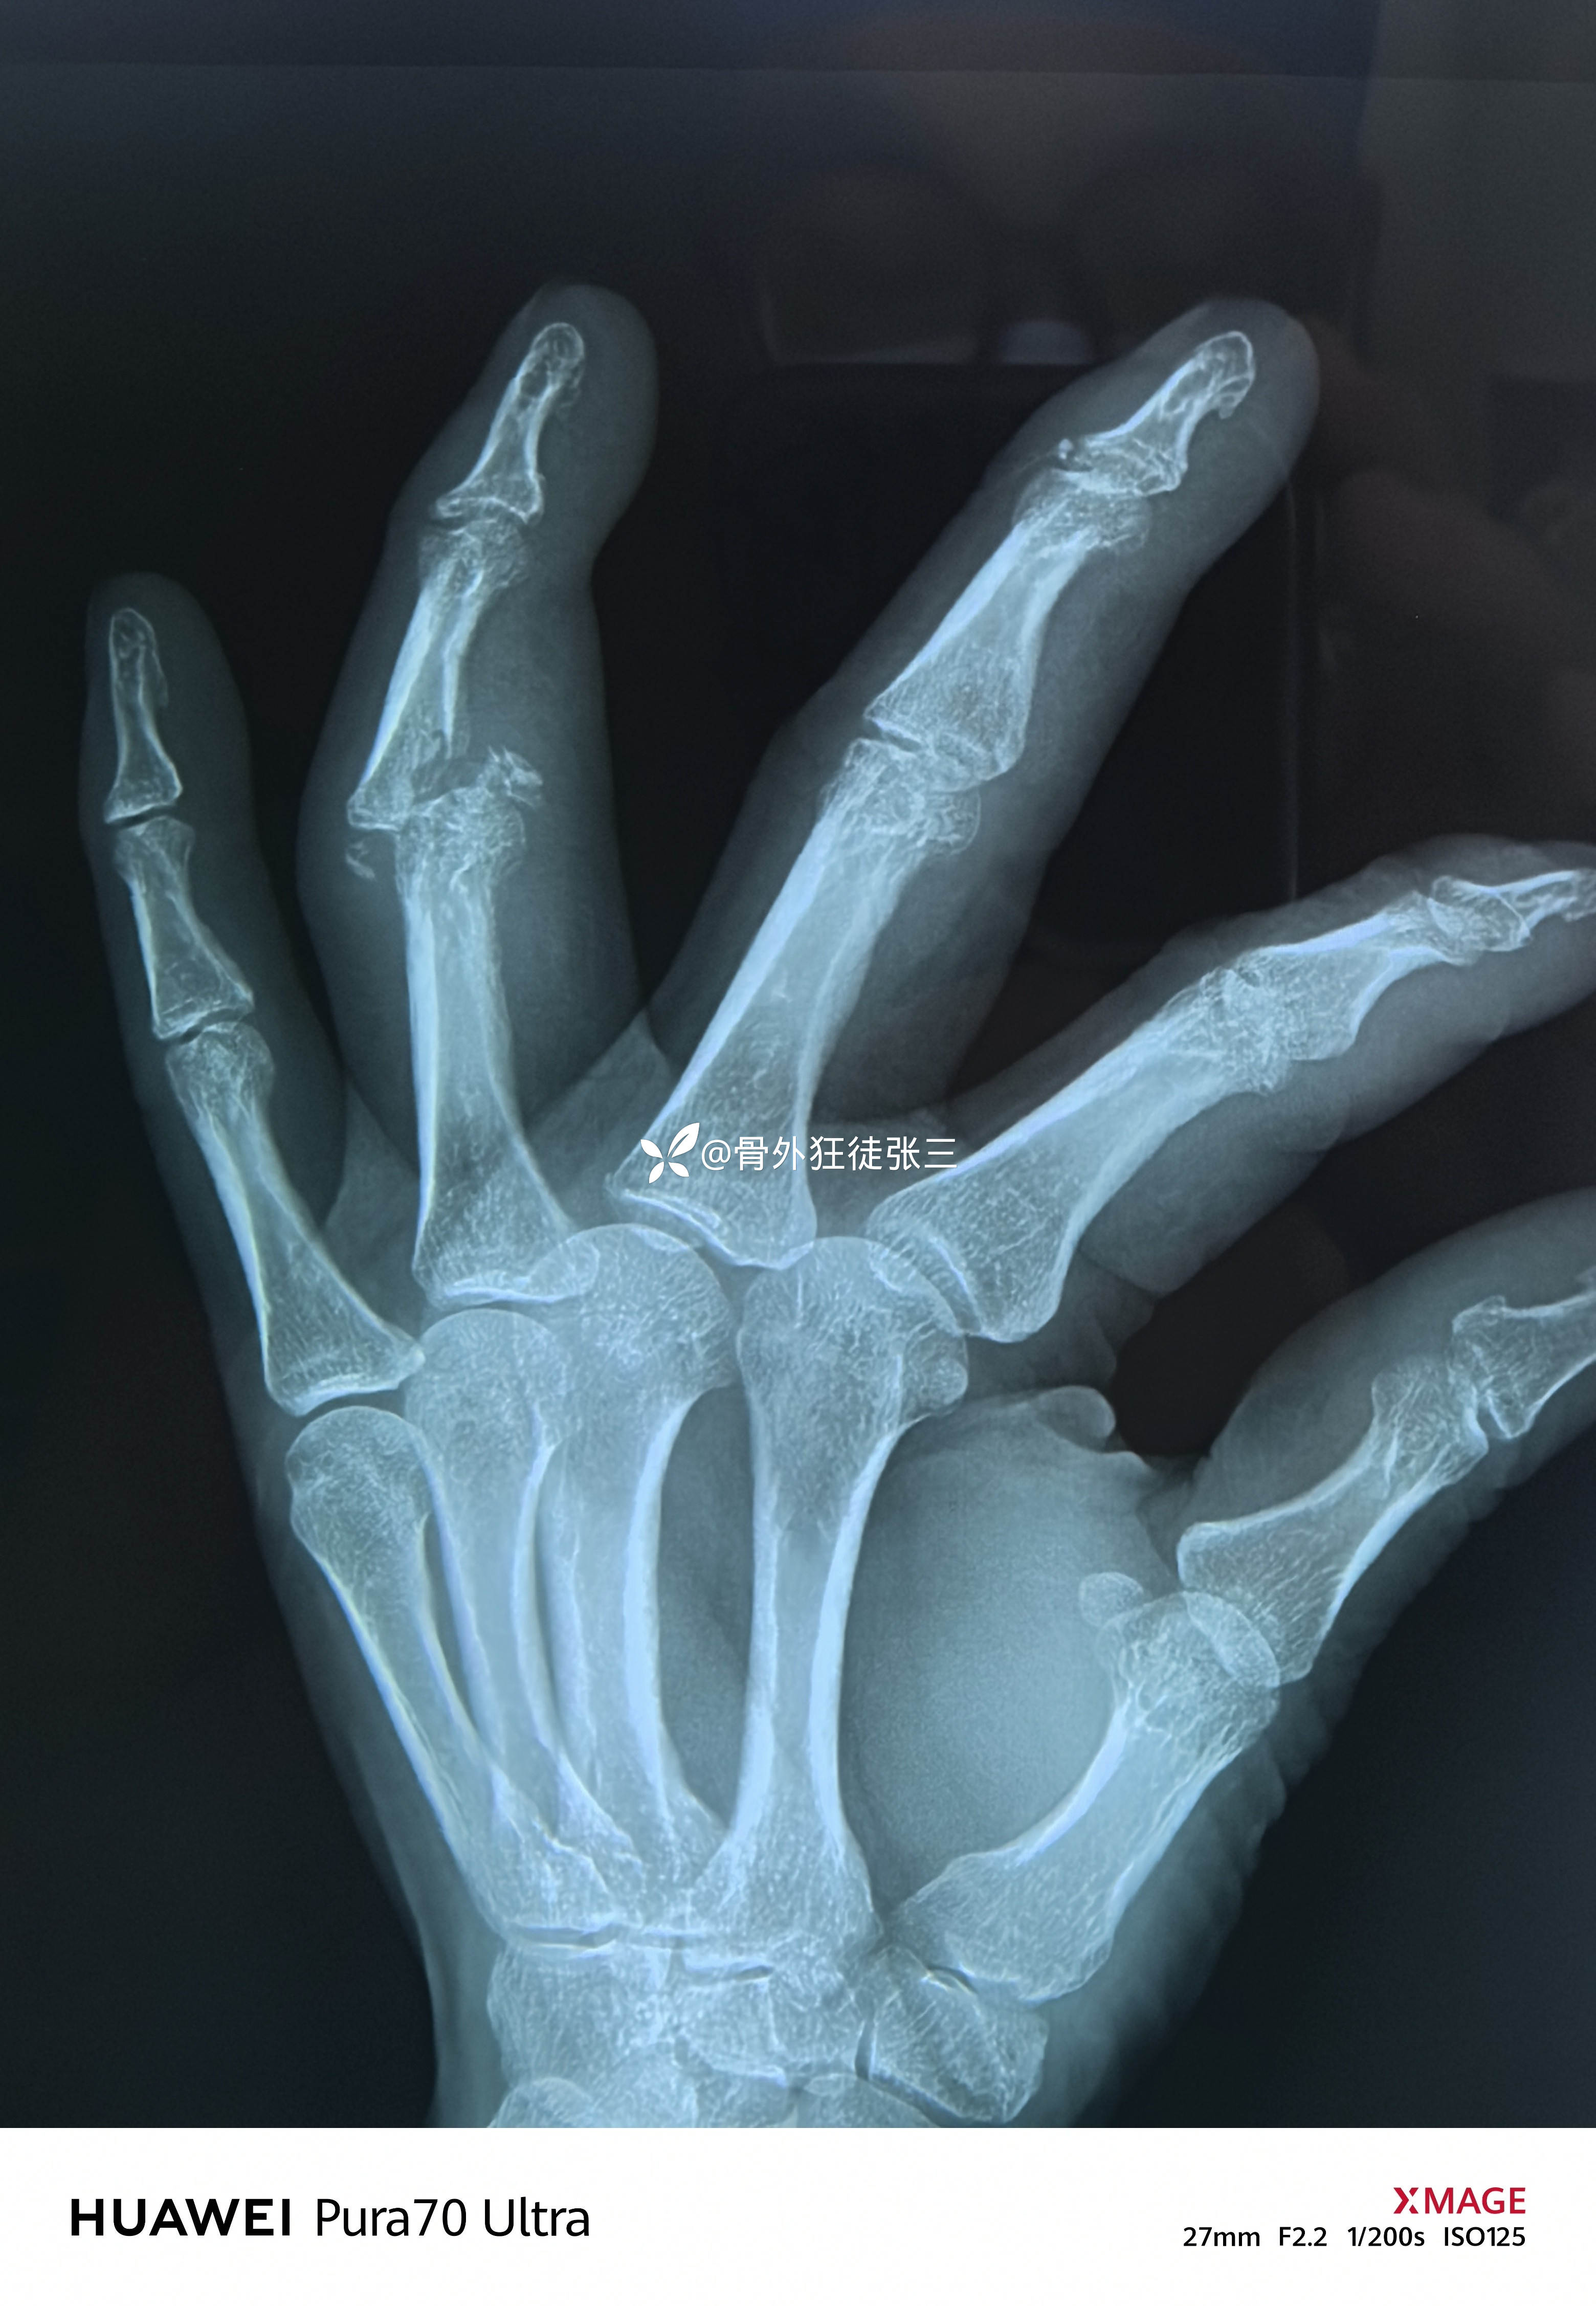

X线显示近指间关节后脱位

中节指骨基底掌侧浅屈肌腱止点骨折

左手环指中节指骨Pilon骨折